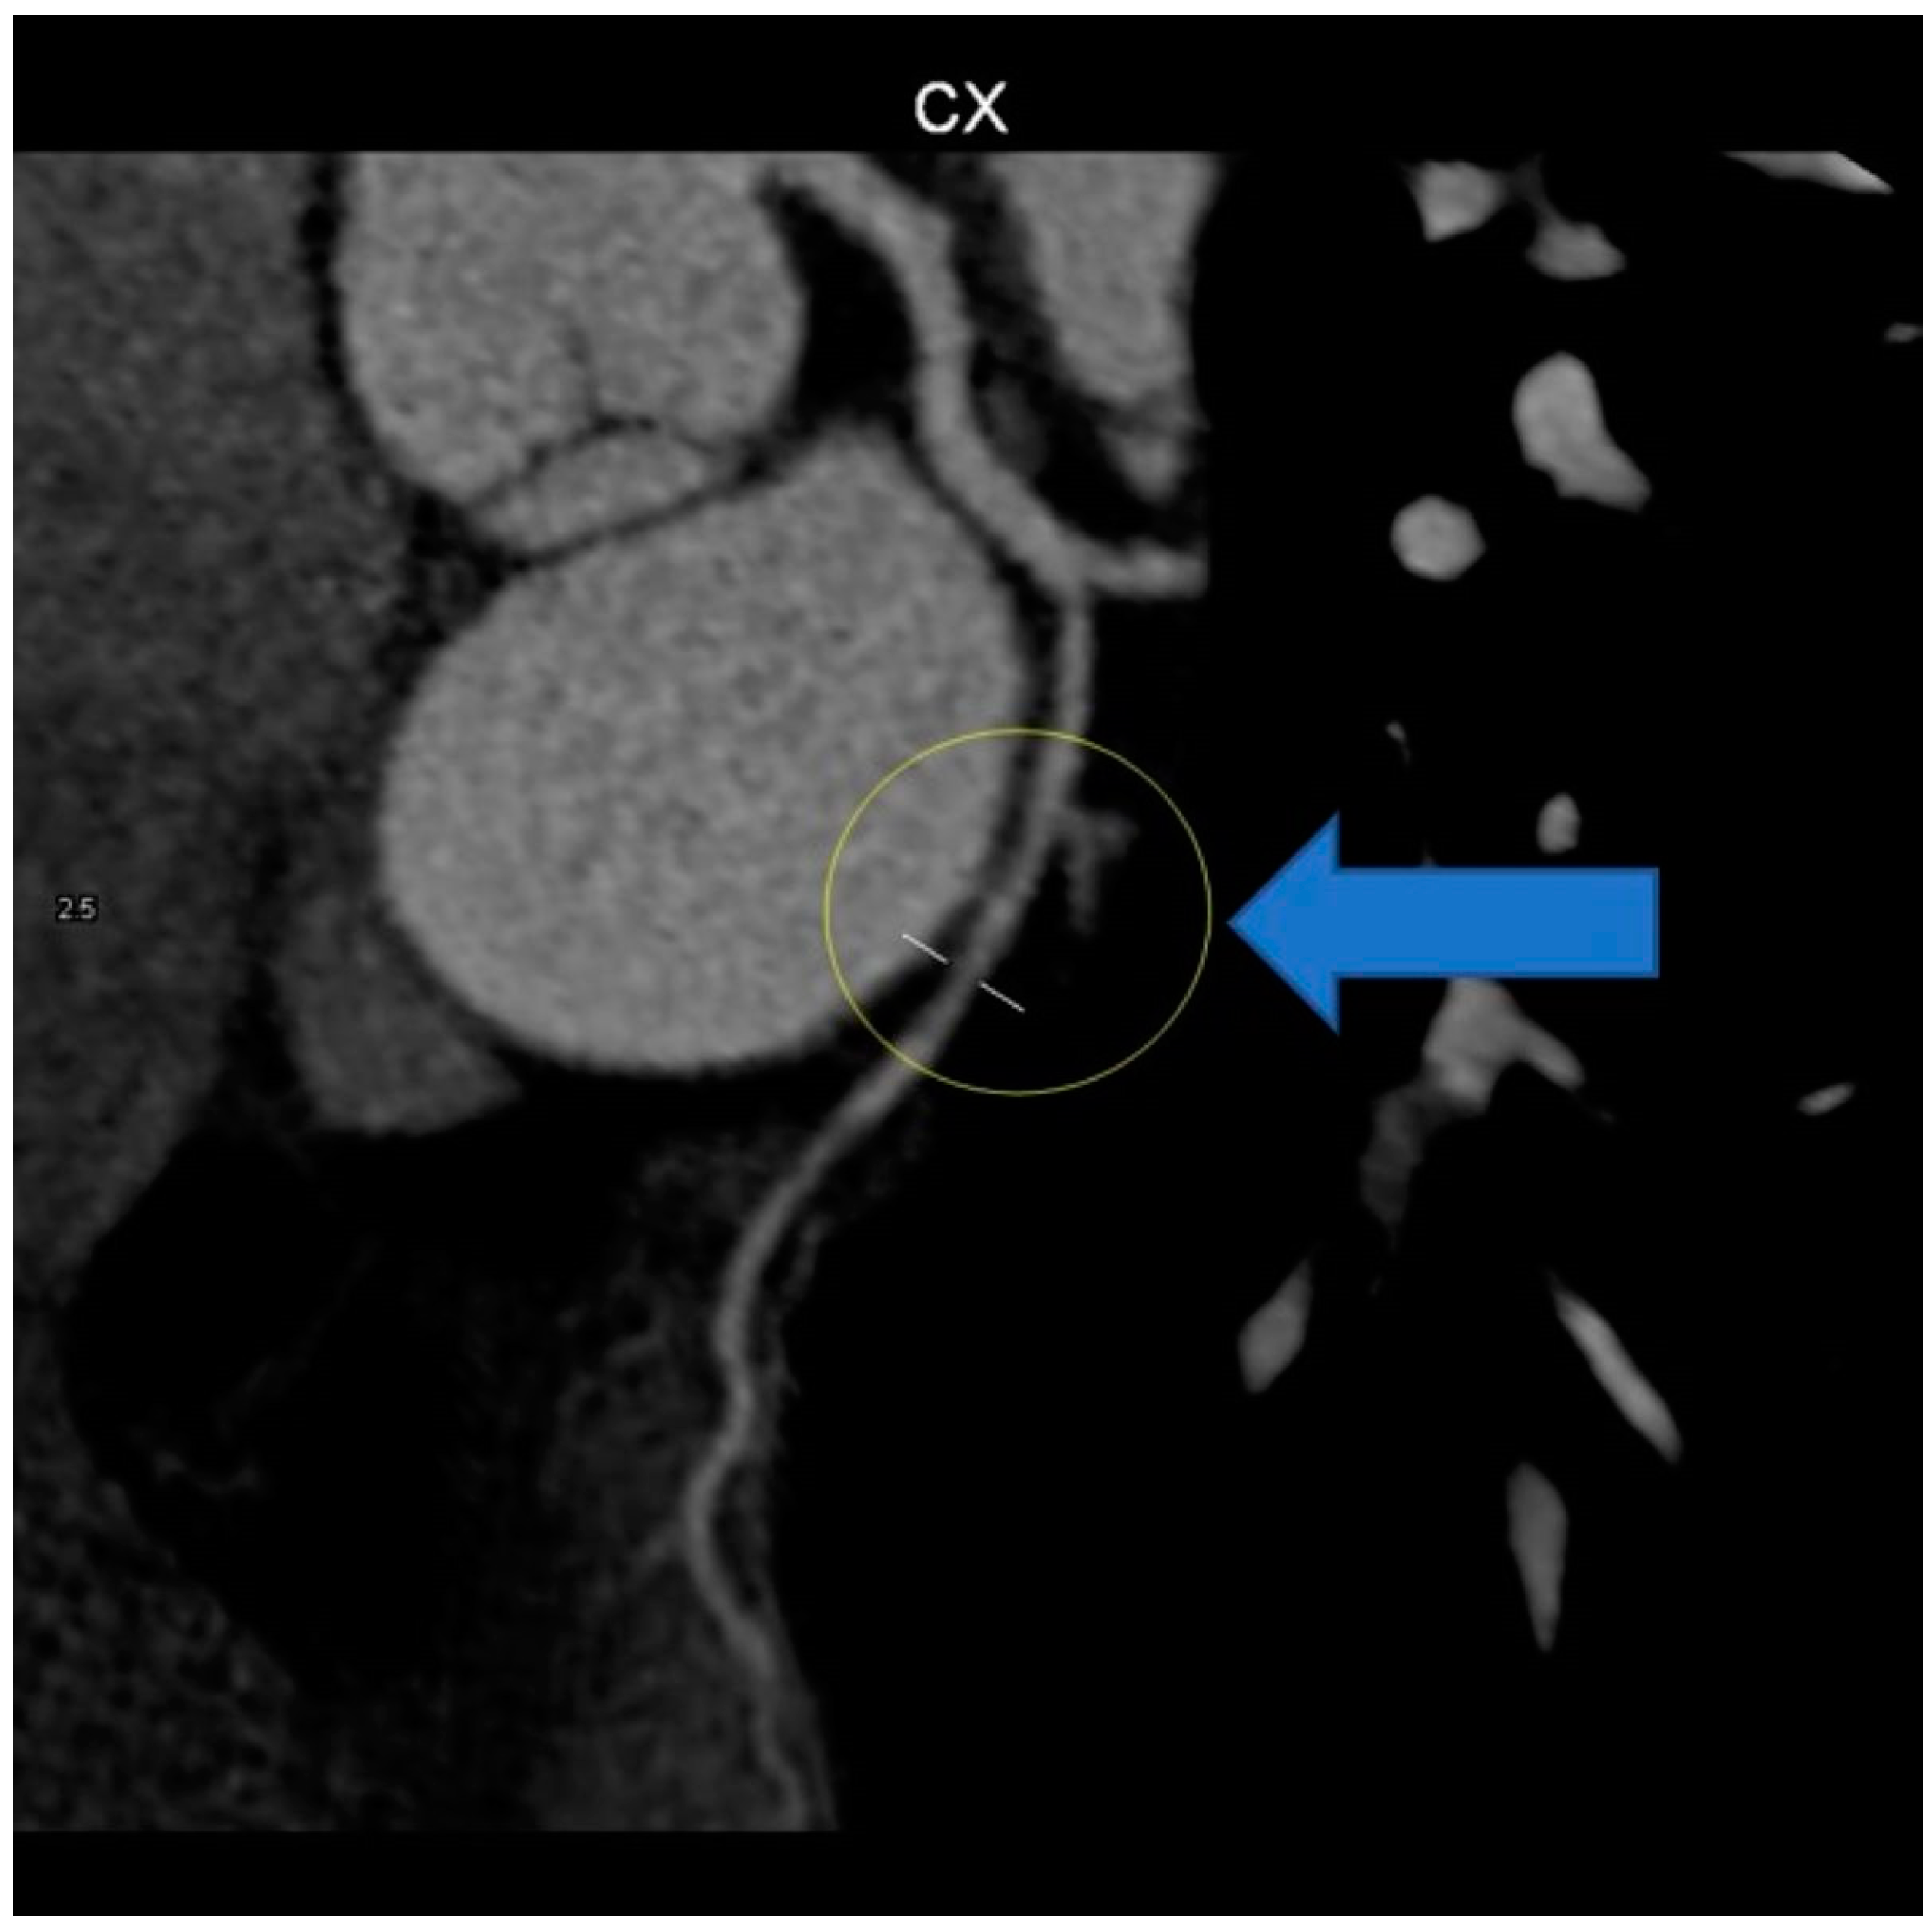

Due to the marked anxiety of the patient and the characteristics of the chest pain, a new multi-slice 128 × 0.5 mm ECG-modulated CT coronary angiography was planned, which revealed an average heart rate of 57 bpm; normal coronary artery origin; right-dominant coronary system; dominant RCA with a single calcific spot in the proximal segment, no significant stenosis; posterior descendent artery (PDA), posterior left ventricular artery (PL), and ramus intermediaris (RM) without stenosis; no atheromatous plaque; short, bifurcated LM, without stenosis; LAD and diagonals patent, without stenosis, no atheromatous formation; CX with a stenotic lesion in the middle segment, downstream of obtuse marginal artery (OM) origin, due to fibro-lipid plaque, approximately 50–60%; and OM with mixed stenotic atheromatous plaque at origin, 20–25%, while the rest of the course was patent, without stenosis (Figure 7).

Figure 7. CT coronary angiography showing stenosis (arrow).